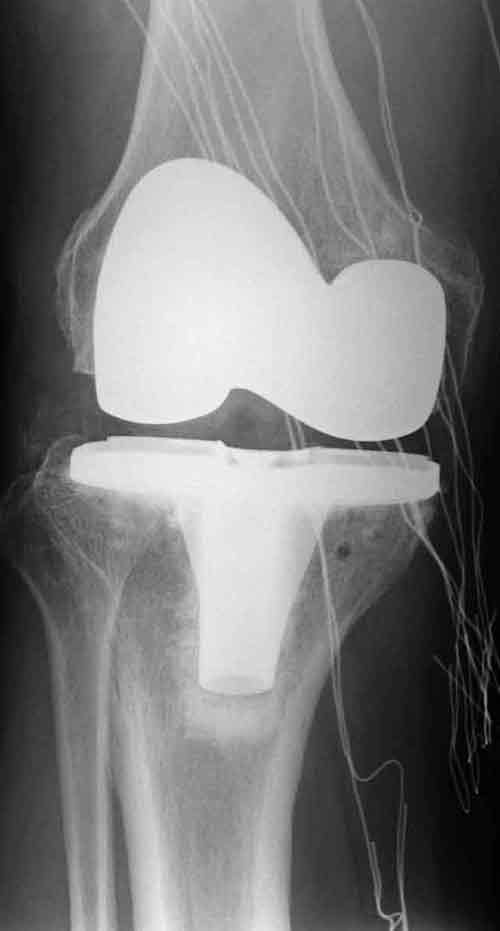

健宫医院骨科成功为一位85岁 老人进行膝关节置换手术

该老人虽然年事已高,但身体素质好,喜欢锻炼。可是严重膝关节骨关节炎严重妨碍了他的生活,身体情况逐渐下降。老人说现在不愁吃喝,生活好了,儿女孝顺,就想提高生活质量,舒心地多活几年,所以强烈要求手术。如此高龄的老人进行膝关节置换国内外罕见。为了手术成功,健宫医院骨科精心进行了手术准备,准备了多种方案,精心操作,手术获得圆满成功。现在老人能够一次遛弯4、5公里,能够踢腿,还能够骑三轮车。

手术后的照片